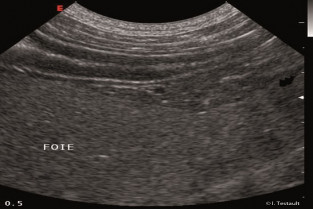

Echographie des affections parenchymateuses hépatiques

Fabrice Conchou

Nathaniel Harran